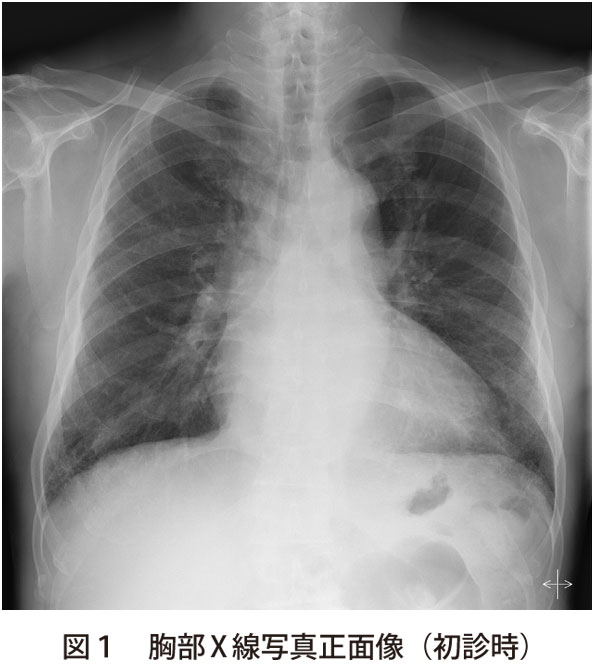

解答 解説 息切れを訴える70歳代男性 実践 画像診断q A 羊土社 レジデントノート 実践 画像診断q A 羊土社 レジデントノート 羊土社